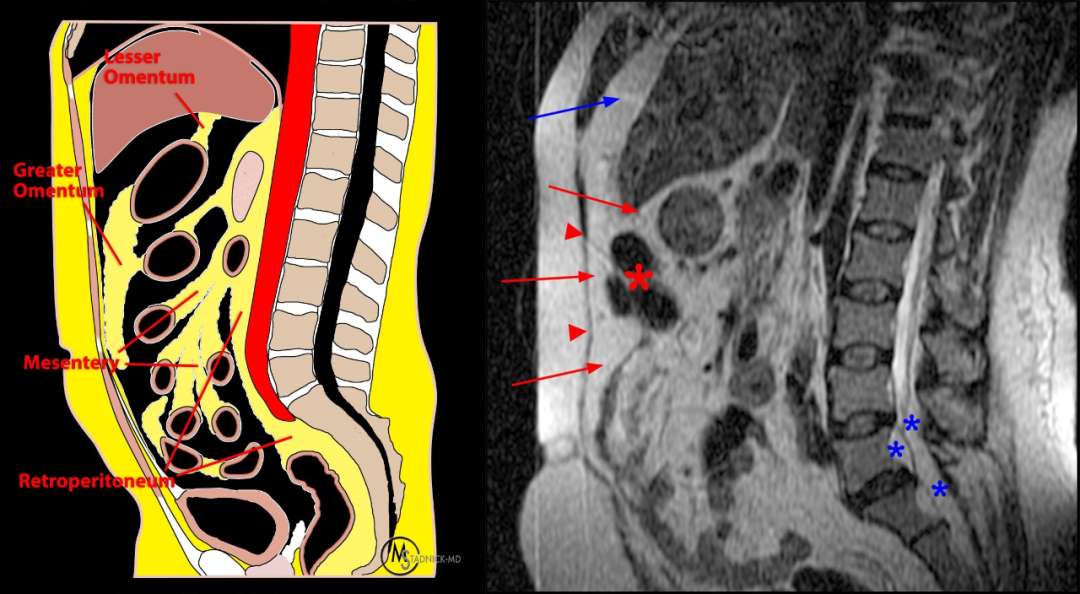

椎管内硬膜外脂肪主要分布于背侧,前缘不超过椎板前缘的连线

矢状位 T1WI 显示硬膜外脂肪组织的正常分布,在腰椎管主要分布于背侧,不连续,在每个椎体层交界处中断(星号)。S1 水平硬膜囊前方有少量正常脂肪组织(箭头),硬膜囊末端终止处,骶管内充满脂肪组织(蓝色星号)

正常的椎管内硬膜外脂肪分布,不会对椎管造成积压

当 MRI 出现轻度至中度 SEL 时,常常会让人怀疑硬膜外脂肪的过度沉积是否确实是患者症状的原因,几乎所有的 SEL 病例都发生在肥胖患者身上,通常为向心性腹部/内脏型肥胖,多余的脂肪组织在脂肪含量较少的部位沉积,如大网膜和小肠系膜。此时,定位像可以帮助我们很好的发现。据报道,对患有 SEL 的肥胖患者实施保守治疗导致体重减轻有可能逆转临床症状,后续 MRI 检查显示硬膜外脂肪沉积减少。

内脏脂肪沉积明显(星号),而后方皮下脂肪组织正常(箭头),与内脏型肥胖相适应

53 岁,男,腰痛和双侧坐骨神经痛,MRI 显示 SEL(蓝色星号)。既有皮下肥胖,也有内脏肥胖。大网膜(长箭头)深至白线和腹筋膜(箭头),浅至横结肠(红色星号)。肝前脂肪垫明显向上(蓝色箭头)。